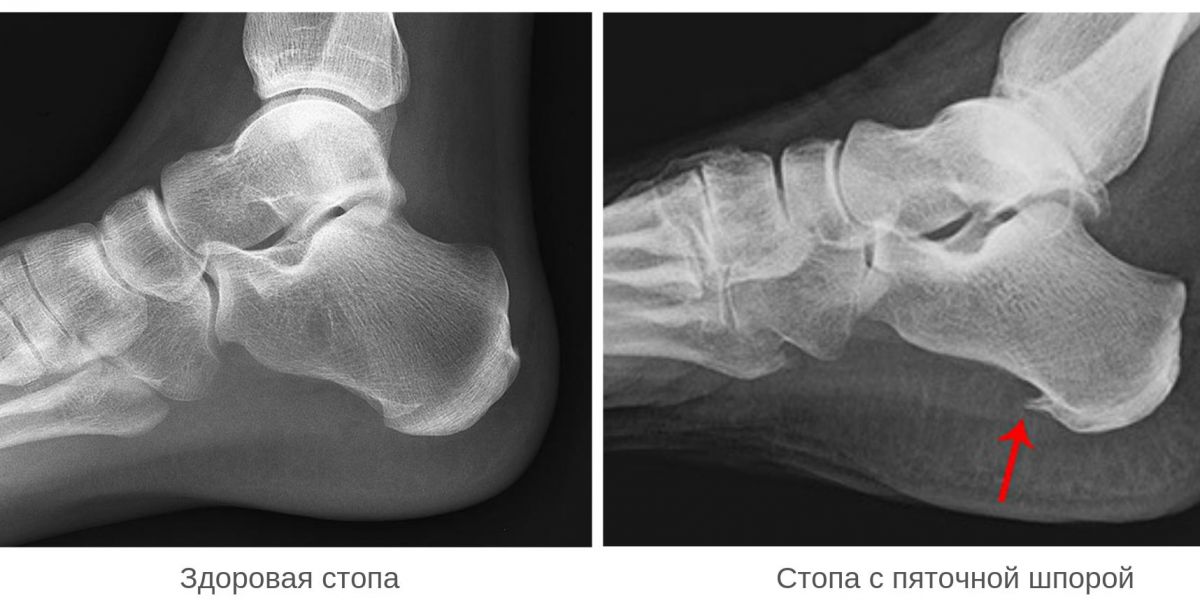

Диклофенак и пяточная . . . Пяточная шпора - это разрастание костной ткани в виде шипа в зоне бугра кости пятки или около ахиллова сухожилия .